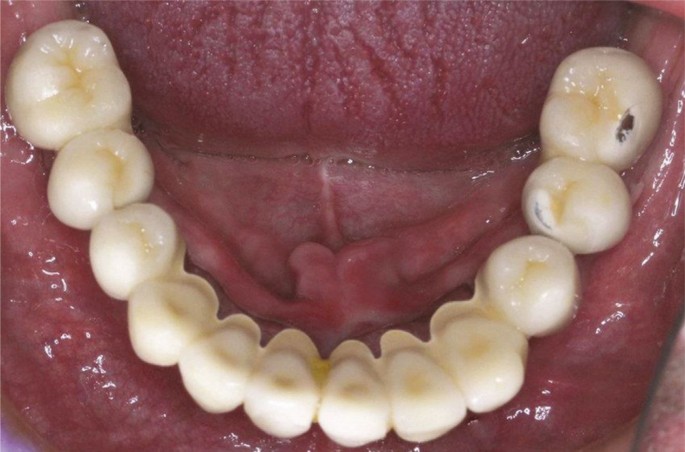

The graded zirconia glass material offers a solution that is both aesthetically acceptable and damage-resistant for posterior dental crowns. They are also a good fit for restorations such as onlays, inlays, crowns, Maryland bridges and fixed partial dentures (FPDs). A straightforward staining method or applying a ceramic overlay in a very thin layer may accomplish this objective. The chipping and fracture of veneers are commonly found as failure causes in porcelain-veneered zirconia dental crowns (Fig. 2). The usage of GZG with external aesthetic glass (e-GZG), as indicated by certain estimates, may increase the durability and give higher protection against veneer chipping and fracture in comparison to porcelain veneered zirconia while still keeping the essential aesthetic attributes.21 A graded GZG structurep with porcelain-veneered zirconia systems displayed a much lower level of reaffirmed resistance against sliding contact fatigue than the graded GZG structure with an exterior glass material that was visually acceptable.21 This innovative GZG with external aesthetic glass e-GZG structure has the ability to make it easier to meet the aesthetic requirements for dental restorations. The opaque and artificially white look of the monolithic Y-TZP is successfully contrasted by the fact that the exterior glass layer displays outstanding translucency and provides a variety of shade choices. In addition, the colour of the e-GZG may be altered by adjustments in the glass's composition, making it a versatile material. Incorporating a translucent Y-TZP into the composition of the material is another way to increase the level of transparency possessed by the material. The e-GZG has a glassy surface and a lower modulus and hardness than other materials. The property, as mentioned above, serves as a protective barrier against excessive abrasion that the rigid and homogeneous Y-TZP material on the opposing dentition may cause. Furthermore, an evaluation has been conducted on the material‘s capacity to withstand contact and flexural damage, and a technique for glass-ceramic infiltration was developed to maintain the materials structural soundness.12 The graded glass-zirconia structure located at the cementation surface of zirconia mitigates bending stresses, consequently enhancing zirconia's flexural structure. The graded structure can offer resistance against fatigue sliding damage due to its inherent design.

Chipping fractures in porcelain-veneer dental prosthesis. Reprinted from The Journal of Prosthetic Dentistry, vol 122, Papaspyridakos et al., ‘Complications and survival rates of 55 metal-ceramic implant-supported fixed complete-arch prostheses: A cohort study with mean 5-year follow-up', pp 441-449, copyright 2019, with permission from Elsevier53